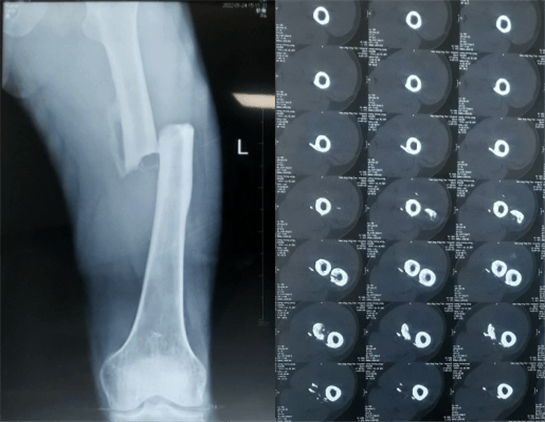

患者:男性,43歲,左股骨干骨折髓內(nèi)釘內(nèi)固定術(shù)

醫(yī)院:南京應(yīng)天骨科醫(yī)院

術(shù)前檢查